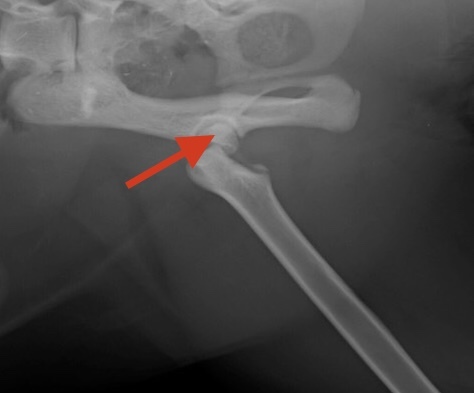

心配していた残った左足股関節のピンで留めていた部分が外れて再手術になりました。

ピンを抜き骨頭を切除する手術になります。

ここの部分です。以前のレントゲンです🙏

半球状の部分をカットしました。